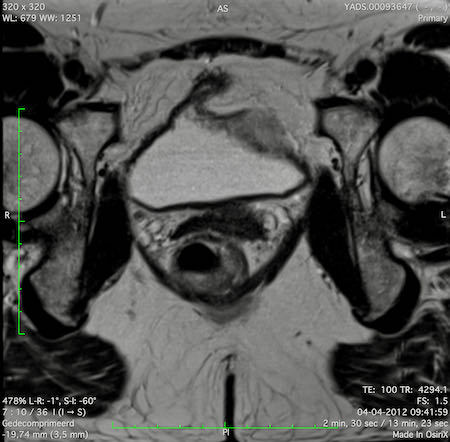

Hình ảnh

Các hình ảnh được cung cấp cho thấy ung thư biểu mô tế bào nhẫn với tình trạng dày lan tỏa thành trực tràng, hình ảnh bia bắn điển hình, và sự xâm lấn mỡ mạc treo trực tràng.